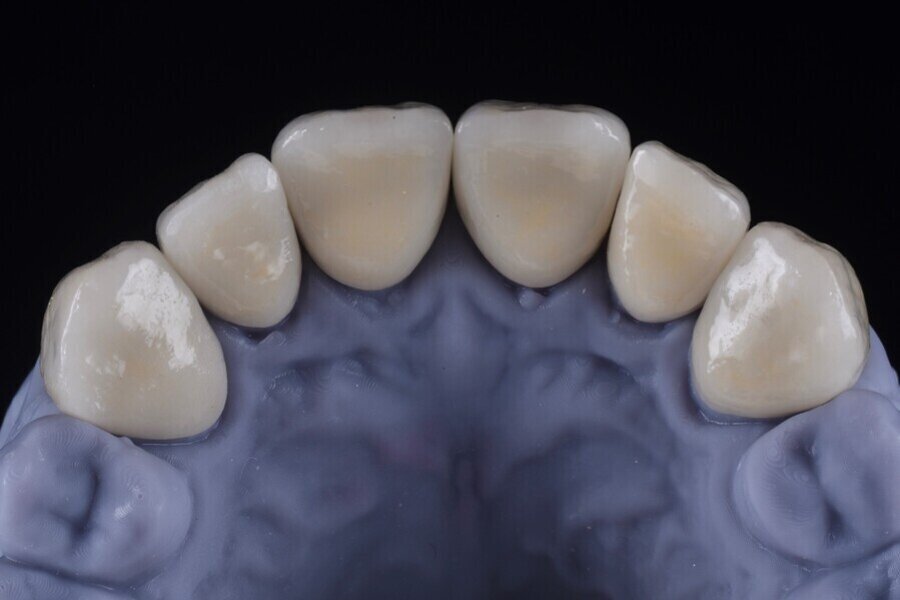

V rámci digitálního designu navržené rekonstrukce byla provedena částečná redukce dolní poloviny bukální plochy plánovaných korunkových náhrad, aby bylo umožněno vrstvení keramiky pro dosažení co nejlepšího estetického výsledku (obr. 12 a 13).

Obr. 12: Kontrola tloušťky.

Obr. 13: Konečná rekonstrukce (s prostorem pro frontální stratifikaci).

Obr. 14a, b: Finální náhrady.